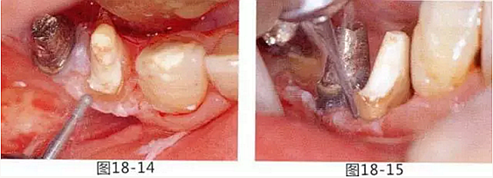

圖18-14 使用圓頭金剛車針進行骨外科處理。

圖18-15 使用鎢鋼車針去除殘留在牙根面的纖維。